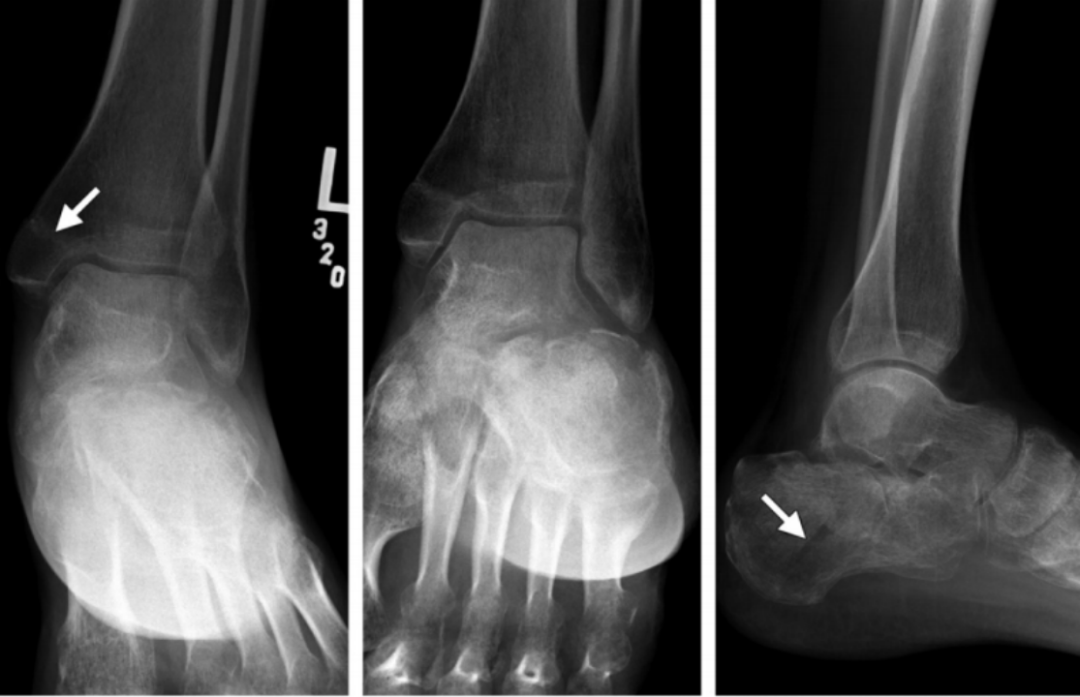

4、旋前(外翻)外展损伤(简称 PA)

伤足处于旋前位,而距骨是外展,三角韧带处于紧张,分为三度:

旋前外展损伤

Ⅰ 度:首先发生的是内侧三角韧带断裂或者内踝的撕脱骨折。

I 度损伤 X 线显示:内踝水平骨折;侧位片腓骨无骨折。

Ⅱ 度:距骨外展的力量继续作用于下胫腓关节,导致下胫腓前、后韧带的断裂或者撕脱骨折 ,骨间韧带、骨间膜撕裂。

II 度损伤 X 线片显示:腓骨无骨折,内踝间隙变宽,提示三角韧带断裂;侧位片显示后踝骨折(箭头)。

Ⅲ 度:距骨外展的力量作用于腓骨,使其外侧受到压力,内侧受到张力,导致腓骨在胫骨关节面附近发生短斜形骨折,主要骨折线基本呈横行,常伴有三角形小骨片,或者外部粉碎型的骨折;甚至可以伴有胫骨远端关节面外侧部分的压缩骨折。

III度损伤X线片显示:内踝间隙增宽,提示三角韧带断裂,胫腓骨间隙增宽,提示下胫腓联合断裂;腓骨斜向骨折,外侧高,内侧低;侧位片显示后踝骨折(箭头)。